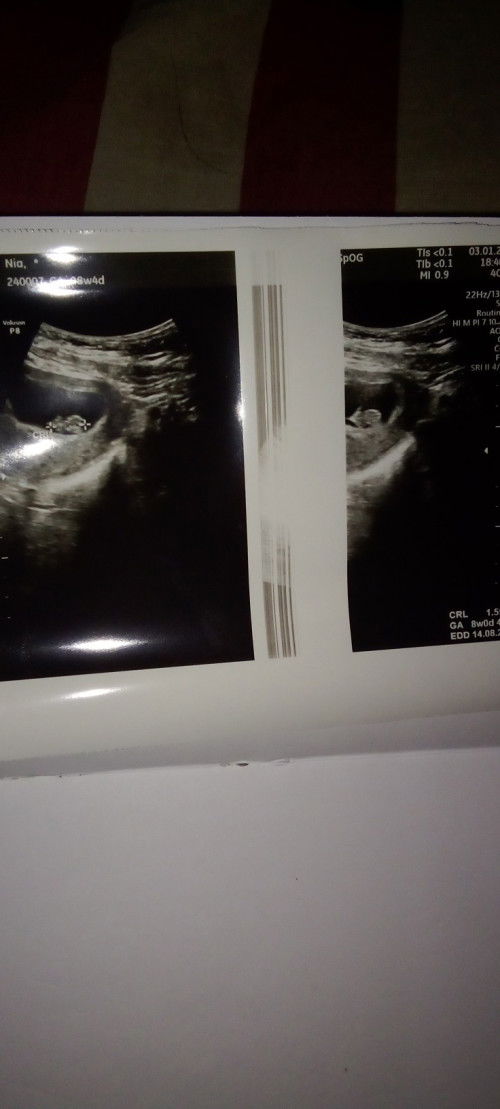

Baru sempat USG di umur 8w4d

MLM bundaa Dsni ad yg samaan gak USG di 8week udh jelas gini gakk? Btw ini doktr andalan aku dr hamil anak pertama sudah terlalu cocok soalnya detile Skali pnjelasannya ❤️😇🙏 smoga sehat sllu ya mom ❤️